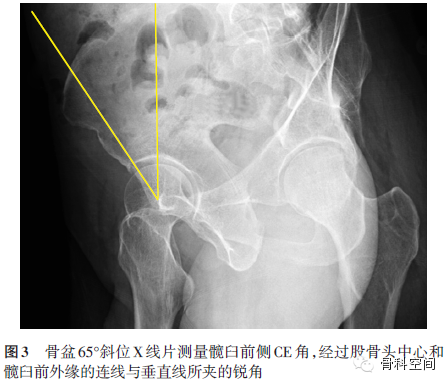

(二)骨盆65°斜位X线片[13]:测量髋臼前侧CE角,观察髋臼前覆盖以及该位置的关节间隙状态(图3)。